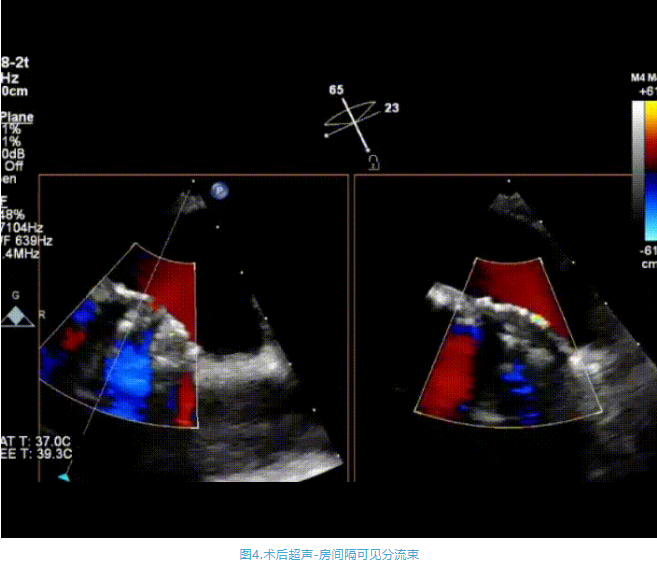

術中首先在局麻下穿刺股動脈、股靜脈,完成心導管檢查評估后轉為全麻,在食道超聲引導下穿刺房間隔,穿刺成功后將加硬導絲送入左上肺靜脈建立軌道,根據患者病情行球囊預擴張后植入6mm孔徑房間隔造孔支架,經透視及食道超聲評估支架左右盤展開良好,夾持于房間隔兩側,固定穩定、位置良好,食道彩超顯示房水平右向左為主分流,分流孔直徑符合預期大小,心導管檢查評估達到預期效果,釋放造孔支架。術后12h患者下床活動,恢復順利,擬于近日完善術后評估后出院。